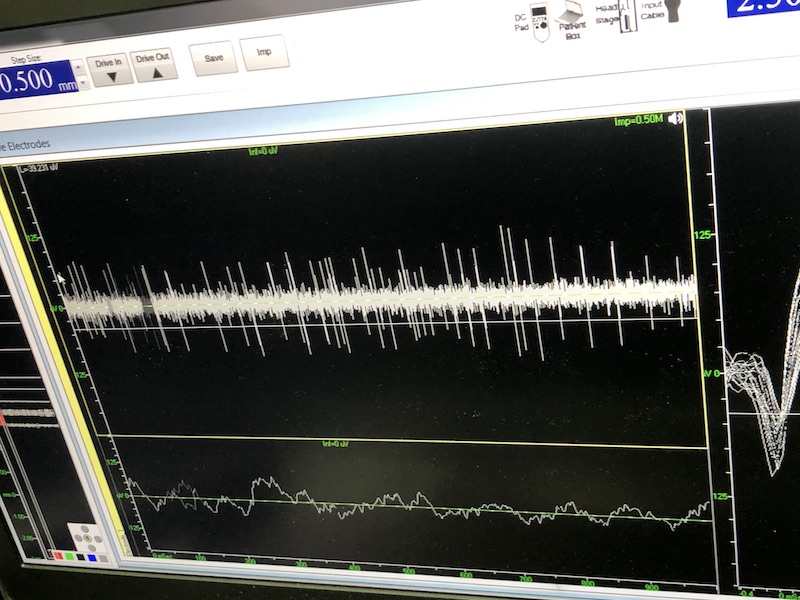

與此同時,檢測電極實時記錄電極末端每一點處的電信號,當電極逐漸接近手術規(guī)劃靶點時,借助電信號的特征,醫(yī)生可以判斷電極是否已經沿長軸植入患者顱內的目標核團,以及植入的準確長度。下圖中,檢測信號屬于典型的核團信號,證明電極已經抵達相對理想的植入位置,記錄下此刻的位置后,即可在相應位置植入刺激電極。

檢測核團信號